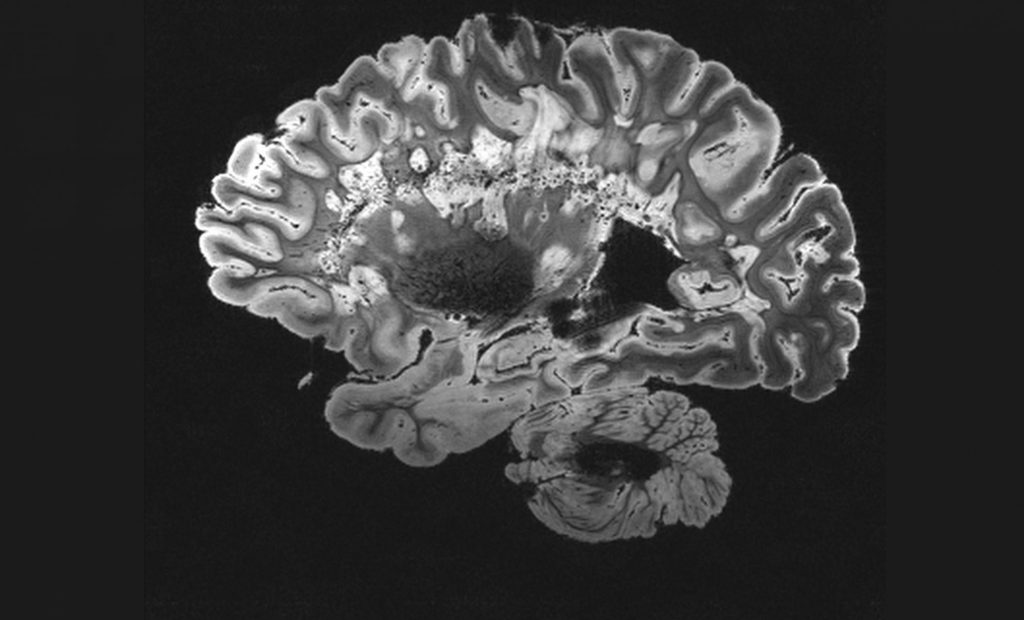

Το γλοιοβλάστωμα είναι ο συχνότερος και πιο επιθετικός καρκίνος του εγκεφάλου και χωρίς θεραπεία οδηγεί στον θάνατο σε διάστημα λίγων μηνών. Ακόμα και με χειρουργική επέμβαση, ακτινοθεραπείες και χημειοθεραπείες, λιγότερο από το 10% των ασθενών ζουν περισσότερο από μια πενταετία.

Το νέο εμβόλιο βασίζεται στον ίδιο μηχανισμό λειτουργίας με τα εμβόλια mRNA για την Covid-19, με τη διαφορά ότι εξατομικεύεται για κάθε ασθενή σύμφωνα με γενετικές αναλύσεις του όγκου.

Το mRNA που περιέχει το εμβόλιο αναγκάζει τα ανθρώπινα κύτταρα να παράγουν καρκινικές πρωτεΐνες, οι οποίες στη συνέχεια μπαίνουν στο στόχαστρο του ανοσοποιητικού συστήματος, το οποίο παράγει αντισώματα κατά αυτών των πρωτεϊνών.